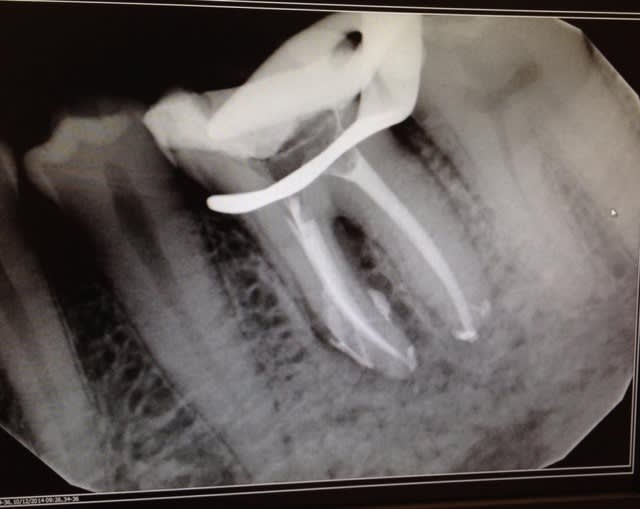

Tient une p'tite 36 (1 rdv, Protaper Gold)

et pas de IC mais tenon fibré collé et couronne zircone pour la suite

Endo 36   pre op kldksv - Eugenol

Endo 36 ssavow - Eugenol

tu as utilisé quel systeme d'obturation ceramik?

Gutta 6% , ciment Kerr, condensation verticale à chaud, rien de spécial